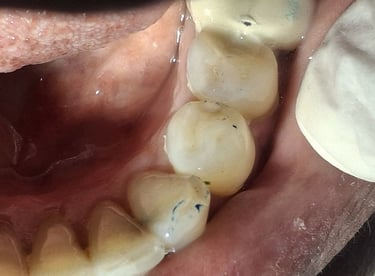

Root Canal Treatment near Shyamal, Ahmedabad

Before

After

All images shown here represent real clinical cases treated at our dental clinic with patient consent.

At Shree Dental Care, we focus on gentle, precise, and well-planned root canal treatment to remove infection, relieve pain, and preserve your natural tooth structure.

Patients from Shyamal and nearby areas of Ahmedabad visit our clinic for comfortable root canal procedures carried out using modern techniques and strict hygiene protocols. The treatment helps eliminate infection from inside the tooth, prevents further damage, and restores normal chewing function.